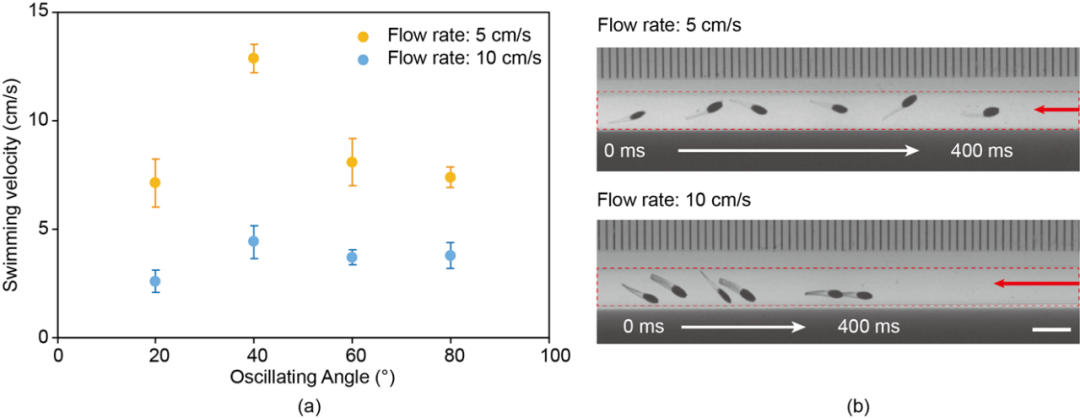

在静态环境实验取得了满意的测试结果后,研究人员开始了机器鱼的“逆行”之旅:

磁驱软体鱼在细管中的逆游性能

如图中所示,当磁场的振荡角为40°时,磁驱软体鱼的最大速度达到13cm/s(水流速度5cm/s),而水流速度加到10cm/s时,可以达到4cm/s的游泳速度。

当研究人员将其放入猪血中,由于血液粘度较高,机器鱼最大游动速度降至11.6cm/s。